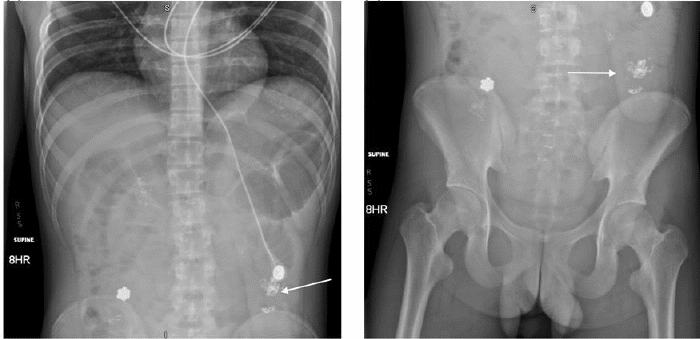

Contrast-enhanced CT scan of the abdomen and pelvis revealed findings consistent with mechanical obstruction. A transition point abutting the abdominal wall at the prior projectile injury site was noted proximal to the ileocolic anastomosis (Figure 3). A small bowel follow-through demonstrated small amounts of contrast in the distal small bowel loops at an 8-hour delay, indicating possible incomplete obstruction (Figure 4). Following discussion with the patient and guardian, a decision was made to perform a re-exploratory laparotomy.

Figure 4. Small Bowel Follow-Through Radiographs Demonstrating Delayed Contrast Progression. Published with Permission

Small bowel follow-through radiographs, obtained after an 8-hour delay following oral contrast ingestion, revealing a trace amount of contrast in the distal small bowel (white arrow). (Left) Upper abdomen view and (right) lower abdomen view